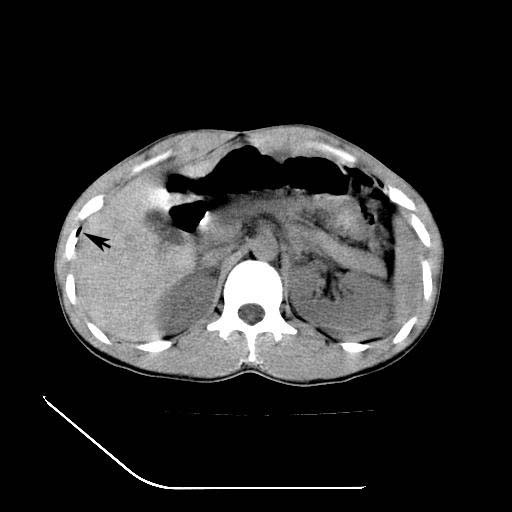

12月7号病人尿量200ml/24h 急查双肾ct

左肾挫裂伤并肾周血肿;

左肾挫裂伤并肾周血肿

支持 : 左肾挫裂伤并肾周血肿

支持:1、左肾挫裂伤并肾周血肿;

2、少量腹水;

3、左肾旋转不良;

4、反射性肠淤张。

除了1:左肾挫裂伤并肾周血肿;

2:少量腹水

第二次ct检查后:临床医生腹水穿刺后考虑肠系膜动脉破裂,后实行剖腹探查:于空肠距离十二指肠90cm处发现肠管破裂,破裂口较小;修补后关腹。